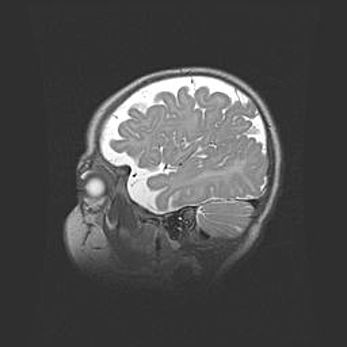

Открытая гидроцефалия.

Возраст: 9 месяцев 12 дней

Вес: 6800 г

Пол: мужской

Окружность головы: 41,5 см

Срок гестации: 28 недель

Гидроцефалия головного мозга у новорожденных имеет характерный признак: опережающий рост окружности головы приводит к визуально хорошо определяемой гидроцефальной форме сильно увеличенного в объёме черепа. Детские неврологи определяют следующие симптомы гидроцефалии у грудничков: выбухающий напряжённый родничок, частое запрокидывание головы, смещение глазных яблок к низу.